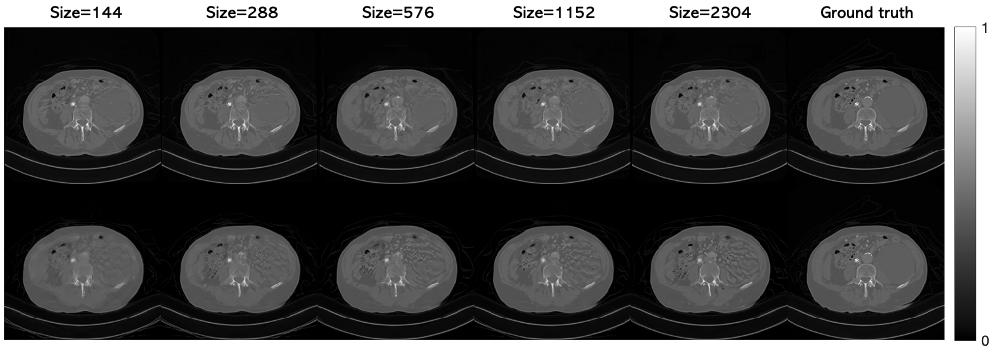

Effect of training dataset size.

A key motivation of this work is large-scale inverse problems having limited training data. To investigate the effects of using small datasets on our proposed method, compared to standard whole image models, we trained networks on random subsets of the CT dataset. Table 5 summarizes the results. Crucially, although the reconstruction quality tends to drop as the dataset size decreased for both the patch-based model and the whole image model, the drop is much more sharp and noticeable for the whole image model, particularly when the dataset is very small. This behavior is consistent with the observations of previous works where large datasets consisting of many thousands of images were used to train traditional diffusion models from scratch.

Table 5: Dataset size effect on CT reconstruction

Dataset Patches Whole image

size PSNR\uparrow SSIM \uparrow PSNR\uparrow SSIM \uparrow

144 32.28 0.841 29.12 0.804

288 32.43 0.837 31.09 0.829

576 33.03 0.846 31.81 0.835

1152 33.01 0.849 31.36 0.834

2304 33.57 0.854 32.84 0.835